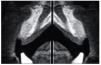

Figura 6. Tomografía computarizada de control realizada a los 6 meses.

Figura 11. Tomografía computarizada de control realizada a los 6 meses.